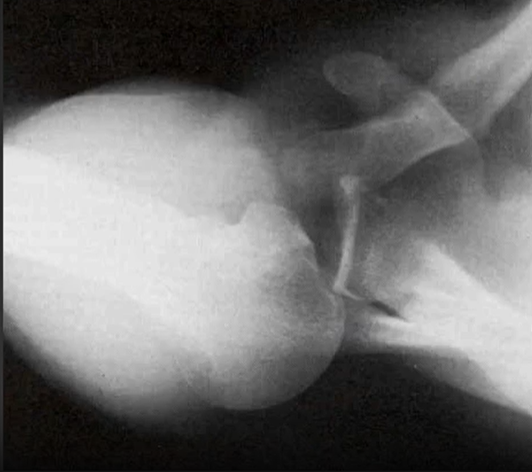

Luxation ant ou postérieure?

Vue axillaire de l'épaule

oui ## Footnote superposition tete humerus et glénoide

Vous faites des rayons-X de l’épaule droite chez cette patiente. Il s’agit d’une vraie AP de Neer. Qu’est-ce que ce RX démontre?

Luxation postérieure de l’épaule.

Il y a superposition de la tête humérale et de la glénoïde sur la vue AP de Grashier